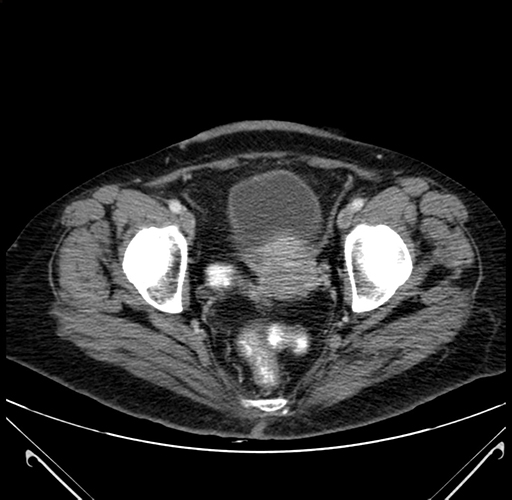

Pre-Chemo: Axial Venous

Axial Venous